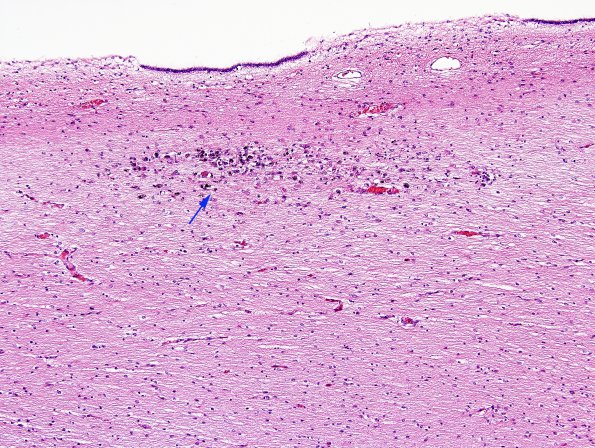

Washington University Experience | MISCELLANEOUS | Familial erythrophagic lymphohistiocytosis | 1C3 Familial erythrophagic lymphohistiocytosis (Case 1) N11 H&E 1 copy.

1C3,4 Several magnifications of periventricular pallor, degeneration, mineralization (arrow) and astrocytosis (H&E)